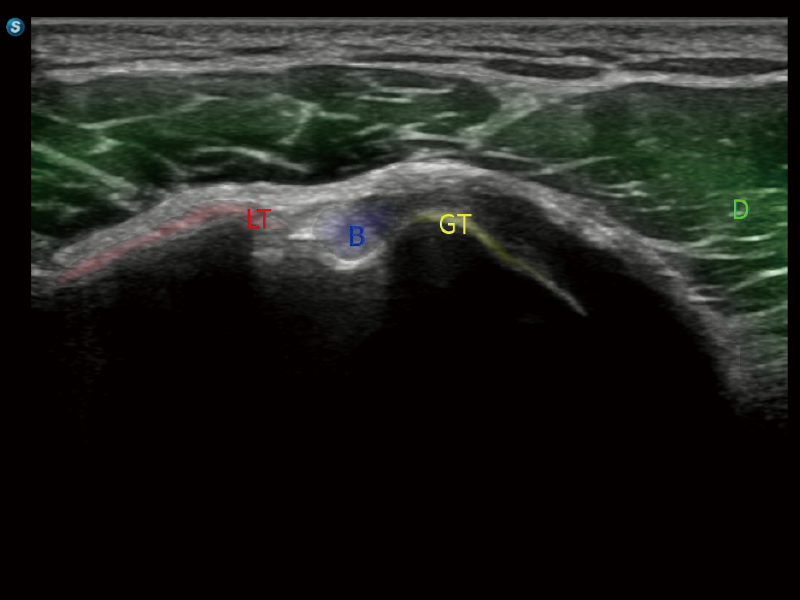

在传统血流的基础上优化扫查和算法策略,能够更好的抑制组织信息,提炼红细胞运动信息,得到更高帧频,高灵敏度和分辨率的血流信号,还原更真实的血流动力学。

通过光照模型,使二维血流显示出立体的效果,增加血流的敏感性、成束性,减少外溢。可以和其他不同的血流技术联合使用,融合不同技术的优势。轻松应对微小血管,增强血流的立体效果,提升视觉敏感性。

通过创新的Matrix E自适应滤波算法,能有效滤除软组织和噪声信号,最大限度保留超低速微细血流的信号;结合超长时间域算法,极大提升细微血流的敏感性和空间分辨率,更真实的反应组织、包块的血流灌注情况。